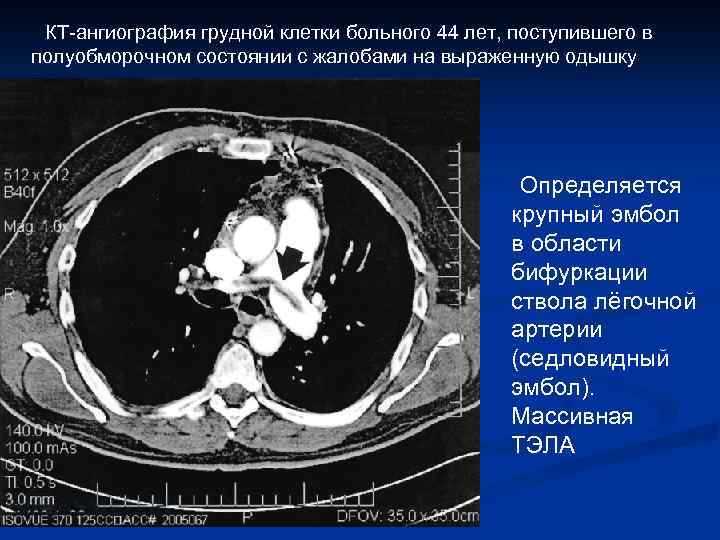

Прямыми признаками ТЭЛА при КТангиографии являются: 1. Полный дефект наполнения (просвет артерии дистальнее эмбола не контрастируется; возможно расширение артерии по сравнению с соседними проходимыми сосудами. 2. Частичный дефект наполнения: в просвете сосуда определяется очаг пониженной плотности, окружённый контрастом. 3. Пристеночный дефект наполнения, который образует с сосудистой стенкой острый угол.

КТ-ангиография грудной клетки больного 44 лет, поступившего в полуобморочном состоянии с жалобами на выраженную одышку Определяется крупный эмбол в области бифуркации ствола лёгочной артерии (седловидный эмбол). Массивная ТЭЛА